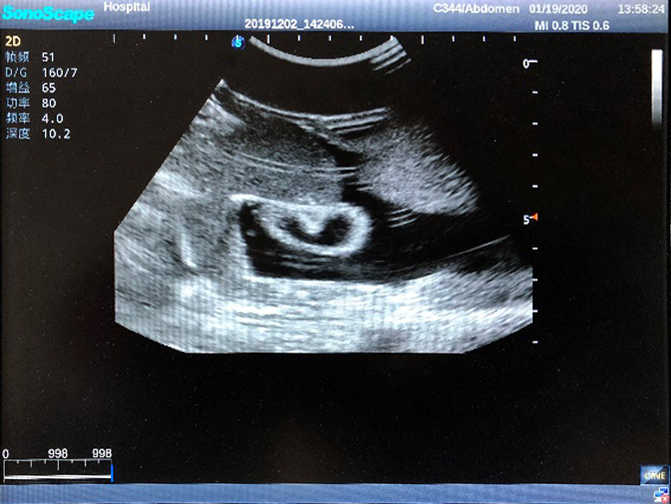

2)  High quality ultrasound image with clear structures like gallbladder, liver, intestines, arteries and veins etc.

3)  Compatible with all types of clinical ultrasound machines

4)  ltrasound gallbladder pathologies like cholecystitis, gallstone and polypoid degeneration

5)  Normal & pathological ultrasound live and intestine models inside

6Durable for repeated use & easy replacement for consumable parts